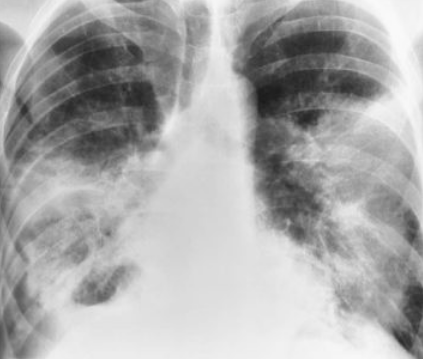

Describe the RA of bronchopneumonia

inflammation produces small patches of consolidation throughout the lungs — no air bronchograms present